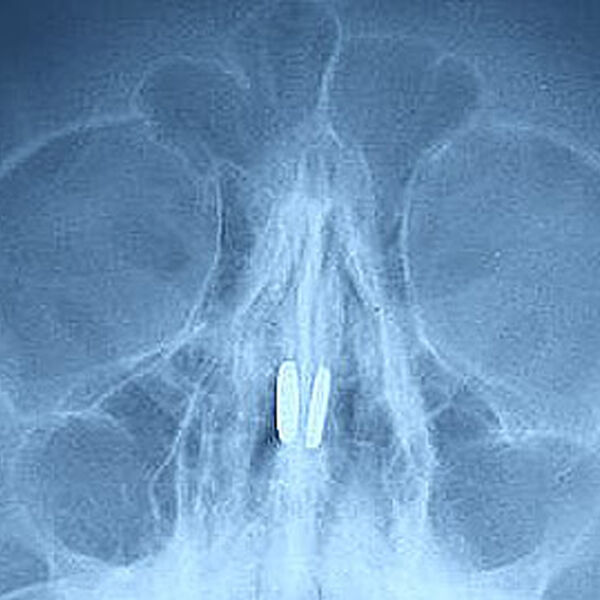

Маленький пациент был доставлен в медицинское учреждение с жалобами на боль в носу и проблемы с дыханием. В ходе обследования в носовых пазухах были обнаружены магниты от игрушки, которые притянулись друг к другу через носовую перегородку.